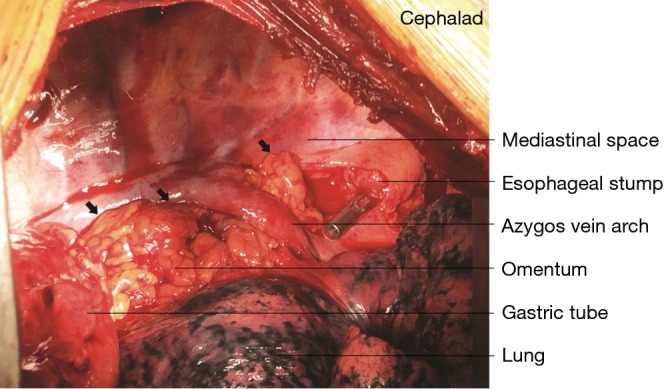

Figure 2.

Pedicled omentum transposed to the mediastinum. Before reconstructing the alimentary tract, the omentum flap (black arrow) was placed within and filled the mediastinal space between the airway and the expected position of the anastomosed gastric conduit.